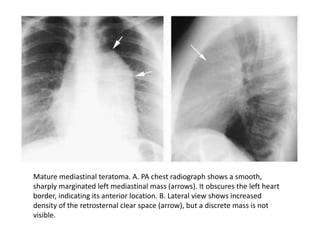

Mature mediastinal teratoma. A. PA chest radiograph shows a smooth,

sharply marginated left mediastinal mass (arrows). It obscures the left heart

border, indicating its anterior location. B. Lateral view shows increased

density of the retrosternal clear space (arrow), but a discrete mass is not

visible.